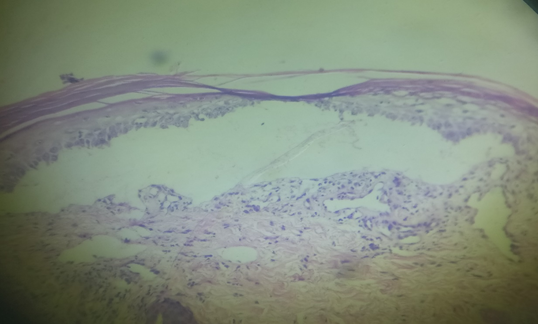

Case report- An 18 year old male presented with oral intolerance to hot and spicy food and itchy reddish lesions over body since 1 month. He denied having any joint pain, fluid filled lesions or similar episodes in past. Examination revealed multiple tender erythematous papules and annular crusted plaques involving the photo-exposed areas of the face, bilateral extremities and trunk with haemorrhagic crusts over lips (Figure 1). Crusted erosions were noted over palmar aspect of fingers and soles. Oral mucosal examination showed erosions over the hard palate and white plaques over the buccal mucosa. Ocular and genital mucosae were spared. Systemic Examination was unremarkable. Clinical differential diagnoses of Erythema multiforme, Systemic Lupus Erythematosus and Rowell’s syndrome were considered. Laboratory investigations showed anaemia (haemoglobin – 7.7gm/dL), with normal liver and renal function tests. Serology revealed a positive rheumatoid factor, anti-nuclear antibody (ANA) with speckled pattern with anti- centromere antibody, anti-Proliferating cell nuclear antigen, anti-Ro antibody, anti- melanosome antibody. 24 hours urine protein levels were normal. Histopathology revealed focal parakeratosis with basal layer vacuolisation. A sub-epidermal bullous lesion was seen. Papillary dermis showed mild perivascular infiltration with mononuclear cells and pigment incontinence. A final diagnosis of Rowell’s Syndrome was reached on the basis of clinico-pathological co-relation and serology. After complete evaluation (including ophthalmological screening) the patient was started on Tab. Prednisolone 40mg per day, hydroxychloroquine 200 mg once daily and photoprotective measures. However he was not compliant with the treatment and presented with multiple episodes of exacerbation over a period of one year which were treated by escalating the dose of systemic steroids. His other systemic evaluation remained unremarkable. A year later, on one of his follow-up visits, the 24 hour urine protein report revealed significant proteinuria (1854.5mg) with deranged renal function tests (creatinine – 2.3). A nephrology opinion was sought and the renal histopathology was consistent with Grade IVa Lupus nephritis. He was administered 6 monthly cycles of intravenous cyclophosphamide (500mg) along with tablet azathioprine 50 mg per day. The patient is currently asymptomatic on cyclophosphamide pulse therapy with stringent clinical and laboratory monitoring.